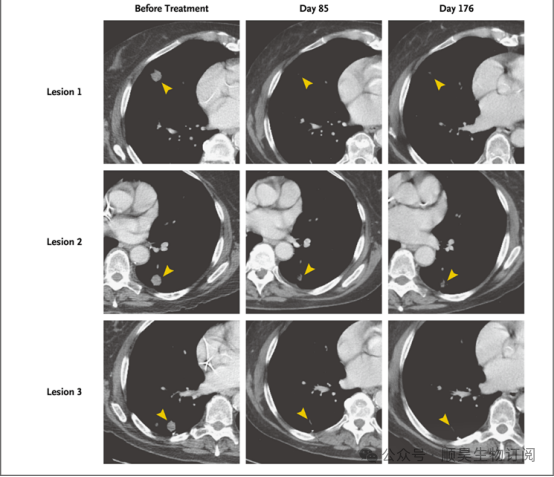

靶向KRAS G12D的细胞受体(TCR)工程化T细胞过继免疫治疗一名胰腺癌患者,患者胸部增强CT。箭头显示治疗前和治疗后的病变

在细胞输入后1个月的第一次临床随访中,CT显示患者的肺转移灶出现消退,客观上肿瘤消退约为62%(根据《实体瘤疗效评价标准》1.1版)。

在细胞治疗6个月后的随访中,肿瘤依然持续消退,此时客观消退约72%。